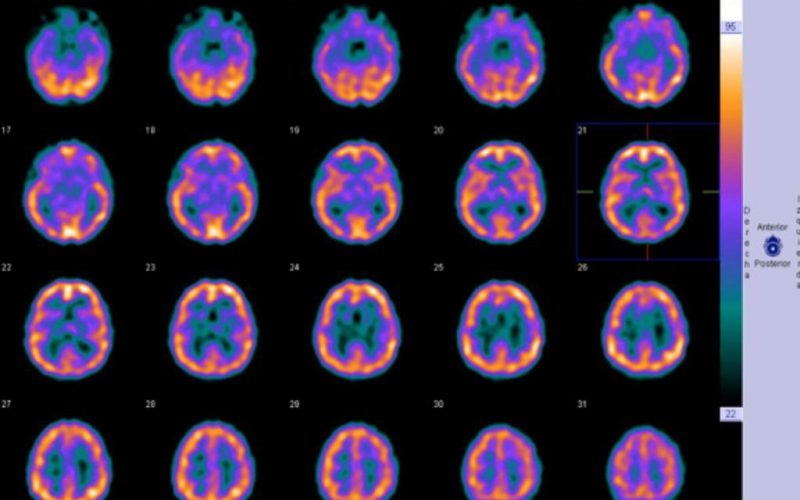

La exploración consiste en la inyección intravenosa de un radiofármaco , deberá estar en reposo durante unos 20 minutos y posteriormente se obtienen imágenes bajo cámara.

La prueba dura aproximadamente una hora.

Diagnóstico de enfermedad de Alhzeimer, Afectación Vascular o Atrofia Cortical entre otras.

Es una prueba GAMMAGRÁFICA en la cual se utiliza una pequeña cantidad de radiactividad para obtener imágenes del cerebro.